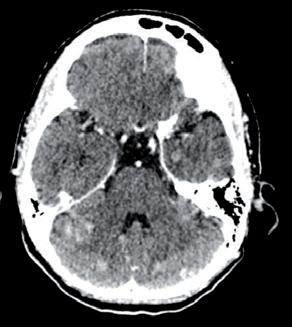

Alla RMN encefalo del 18/02/2022, in sede cerebellare sinistra si conferma la presenza di alterazione sospetta in senso ripetitivo di 15 mm, adesa alla dura madre.

Si evidenzia alterazione osteostrutturale patologica della teca cranica in sede temporo-parietale destra associata a ispessimento lineare della meninge adiacente (figura 3).

TC e RMN encefalo con mdc, febbraio 2022.

Figura